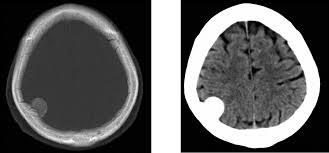

Eficacia de la levodopa para contribuir a la rehabilitación luego de un accidente cerebrovascular

En este ensayo clínico aleatorizado, en pacientes que recibían rehabilitación hospitalaria tras un ictus agudo, la administración de levodopa junto con la rehabilitación estándar no mejoró significativamente la función motora a los 3 meses, en comparación con la administración de placebo. Estos resultados no respaldan el uso de la levodopa para mejorar la recuperación motora tras un ictus agudo. JAMA, 22 de septiembre de 2025.